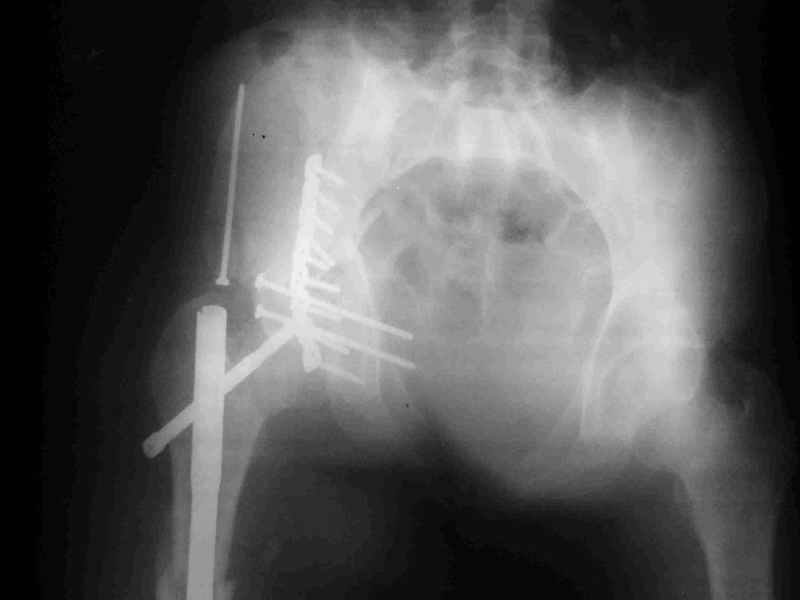

Re: Acetabular fracture

Djoldas kuldjanov, M.D. 02 Сентябрь 2004, 09:05

Диагноз- перелом с вовлечением таза, разрыв правого сакро-илиак сочленения vertical shear injury, перелом крыла подвздошной кости?, перелом ацетабулум Т type или Both column?, перелом шейки бедра, перелом проксимального отдела бедра.

перелом крыла правой подвздошной кости, перелом обеих колонн вертлужной впадины, двусторонний перелом лонных костей (С2.2) повреждение передних связок правого крестцово-подвздошного сочленения,

ипсилатеральный перелом шейки и диафиза бедра.